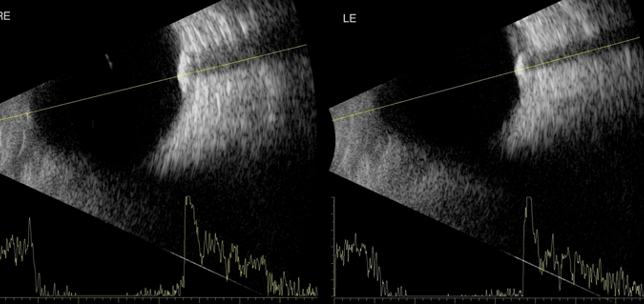

Cortical blindness

Shampa Gupta

JVK Sardar

1st August 2014

Education

Case Reports